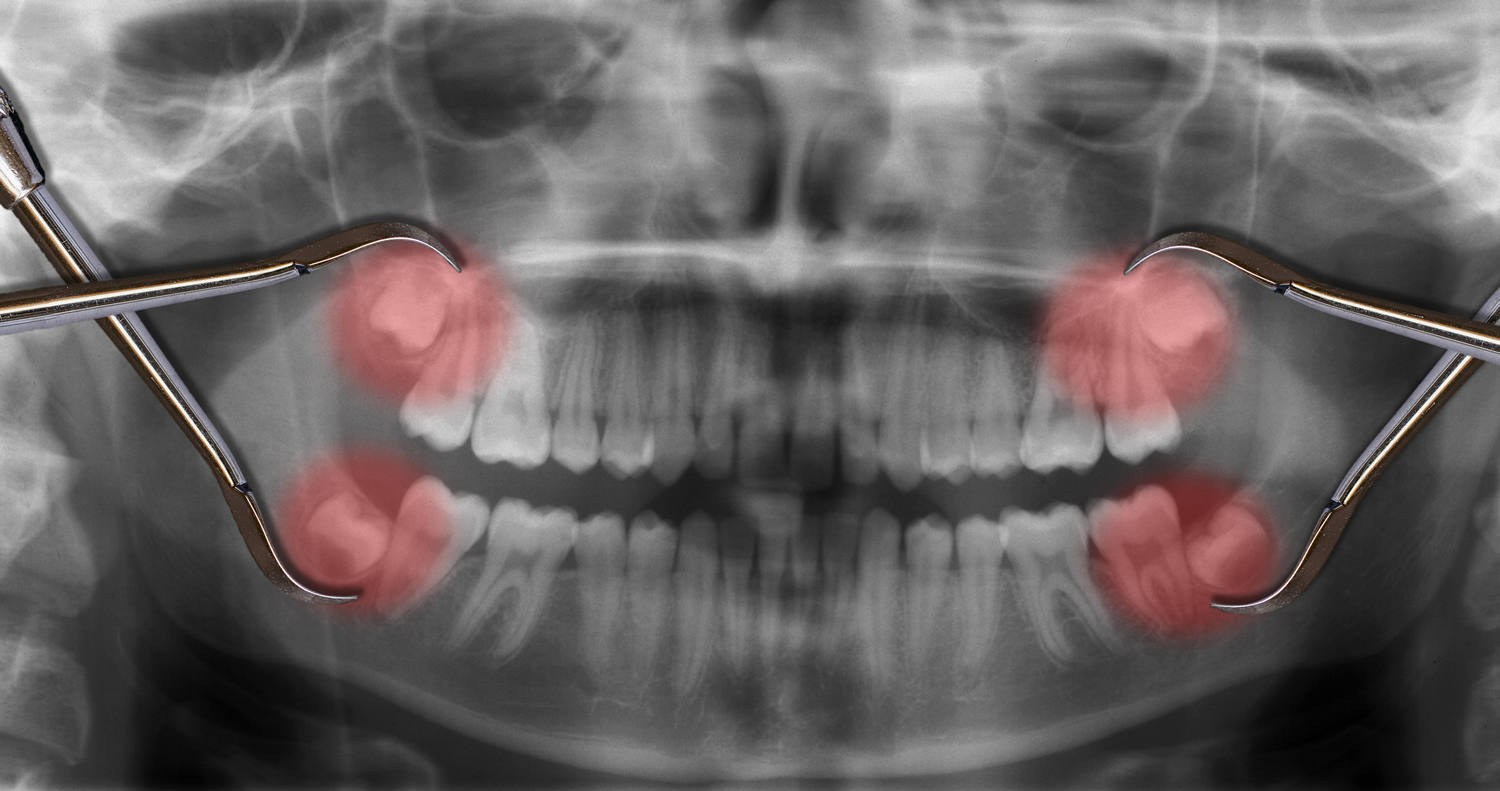

Gömülü diş çekimi, dişlerin normal çıkış yolunu bulamadığı veya kısmen gömülü olduğu durumlarda uygulanan cerrahi bir prosedürdür. Bu durum, diş ağrıları, enfeksiyon riski veya komşu dişlere zarar gibi problemlere yol açabileceğinden, erken müdahale ve uzman kontrolü büyük önem taşır. Gömülü diş çekimi, estetik ve fonksiyonel açıdan uzun vadeli çözümler sunar.

Gömülü diş çekimleri, sadece köpek dişlerini değil; ağız içindeki diğer gömülü veya yarı gömülü dişleri de kapsar. Bu dişler, özellikle bilinen 20 yaş dişi (akıllı dişler) dışında, bazı premolar veya incisivlerin de gömülü olabileceği durumları içerir.

• Dişin konumuna bağlı olarak değişken zorluk derecesine sahip cerrahi teknikler kullanılır.

• Çekim sırasında çevre kemik, sinir ve damar yapılarının korunmasına özen gösterilir.

• Gömülü dişlerin çıkarılması, ağız içi enfeksiyon riskini azaltır ve genel ağız sağlığını iyileştirir.